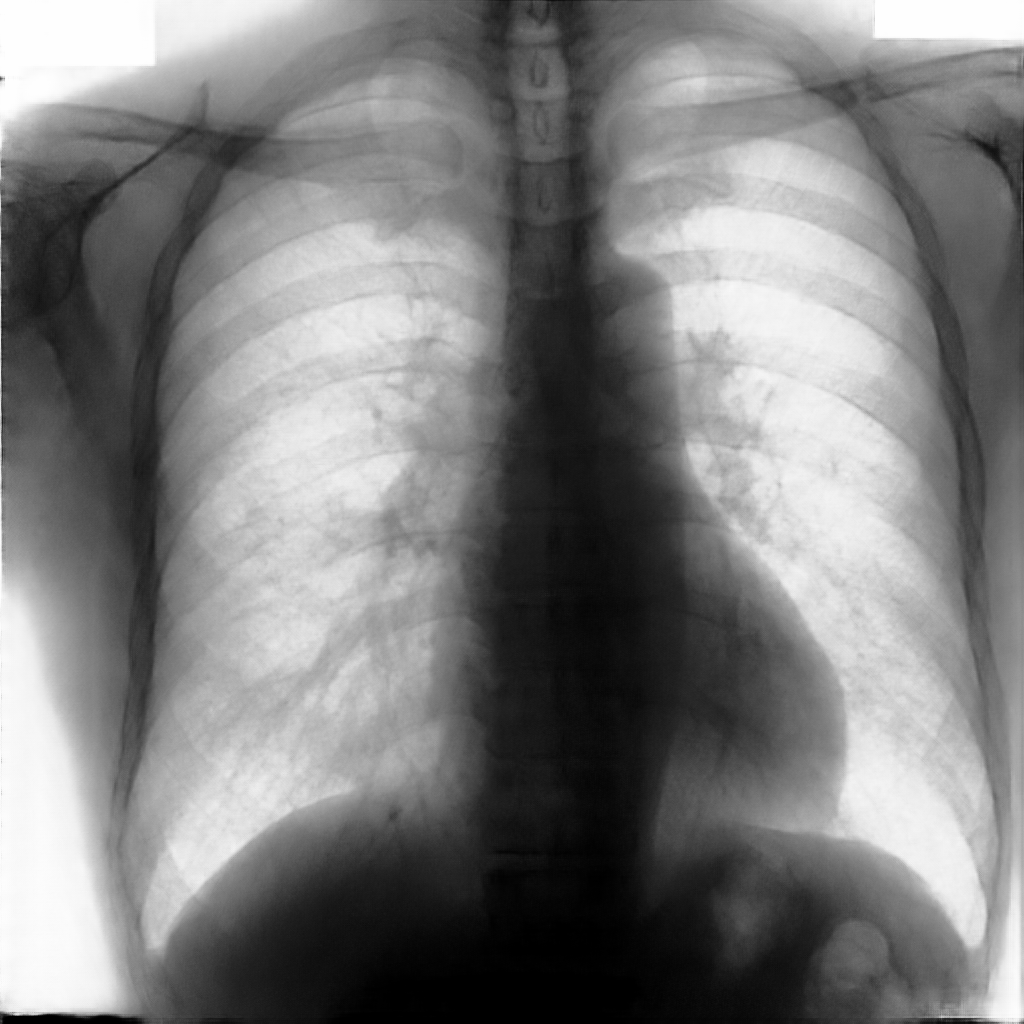

In this section, some examples of images and corresponding segmentations, generated with the approaches described in Section 3, are qualitatively examined. We also report some comments from three physicians on the generated segmentations, to provide a medical assessment of the quality of our method.

Figure 5 and Figure 6 display some examples — randomly chosen from all the generated images — of the label–maps and the corresponding chest X–ray images generated with the three methods described in Section 3, using the FULL_DATASET and the TINY_DATASET, respectively. We can observe that, with the single and two–stage methods, the images tend to be more similar to those belonging to the training set. For example, in most of the generated images there are white rectangles, which resemble those present in the training images, used to cover the names of both the patient and the hospital. Instead, the three–stage method does not produce such artifacts, suggesting that it is less prone to overfitting.

Moreover, in order to clarify the limits of the three–stage method, we assessed the quality of the segmentation results based on three human experts, who were asked to check 20 chest X–ray images, along with the corresponding supervision and the segmentation obtained by the SMANET network. Such images were chosen among those that can be considered difficult, at least based on the high error obtained by the segmentation algorithm. Figure 7 and Figure 8 show different examples of the images evaluated by the experts. The first column represents the chest X–ray image, while the second and the third columns, whose order was randomly exchanged during the presentation to the experts, represent the target segmentation and our prediction, respectively. The three physicians were asked to choose the best segmentation and to comment about their choice. Apart from a general agreement of all the doctors on the good quality of both the target segmentation and the segmentation provided by the three–stage method, surprisingly, they often chose the second one. For the examples in Figure 7, for instance, all the experts share the same opinion, preferring the segmentation obtained by the SMANET over the ground–truth segmentation. To report the results of the qualitative analysis, we numbered the target and predicted segmentation with 1 and 2, respectively, while doctors were assigned unordered pairs to obtain an unbiased result. Then, with respect to Figure 7(a), the comments reported by the experts were: 1) In segmentation 1, a fairly large part of the upper left ventricle is missing; 2) I choose the segmentation number 2 because the heart profile does not protrude to the left of the spine profile; 3) The best is No. 2, the other leaves out a piece of the left free edge of the heart, in the cranial area. Instead, for Figure 7(b), we obtained: 1) The second image is the best for the cardiac profile. For lung profiles, the second image is always better. The only flaw is that it leaks a bit on the right and left costophrenic sinuses. 2) Image 2 is the best, because the lower cardiac margin is lying down and does not protrude from the diaphragmatic dome. Image number 1 has a too flattened profile of the superior cardiac margin. 3) No. 2 for the cardiac profile more faithful to the real contours.

Instead, they reported conflicting opinions or decided not to give a preference with respect to the examples in Figure 8. When they agreed, they generally found different reasons for choosing one segmentation over the other. With respect to Figure 8(a) the comments reported by the experts were: 1) I prefer not to indicate any options because the heart image is completely subverted; 2) Segmentation number 2 is better, even if it is complicated to read because there is a “bottle–shaped” heart. The only thing that can be improved in image 2 is that a small portion of the right side of the heart is lost; 3) No. 1 respects more what could be the real contours of the heart image. Instead, for Figure 8(b) we obtained: 1) I prefer No. 2 because the tip of the heart is well placed on the diaphragm and does not let us see that small wedge–shaped image that incorrectly insinuates itself between heart and diaphragm in image 1 and which has no correspondence in the RX; 2) Both are good segmentations. Both have small problems, for example: in segmentation 1 a small portion of the tip (bottom right of the image) of the heart is missing, in segmentation 2 a part of the outflow cone (the “upper” part of the heart) is missing. It is difficult to choose, probably better No. 1 because of the heart; 3) No. 2 because No. 1 carnally probably exceeds the real dimensions of the cardiac image, including part of the other mediastinal structures.